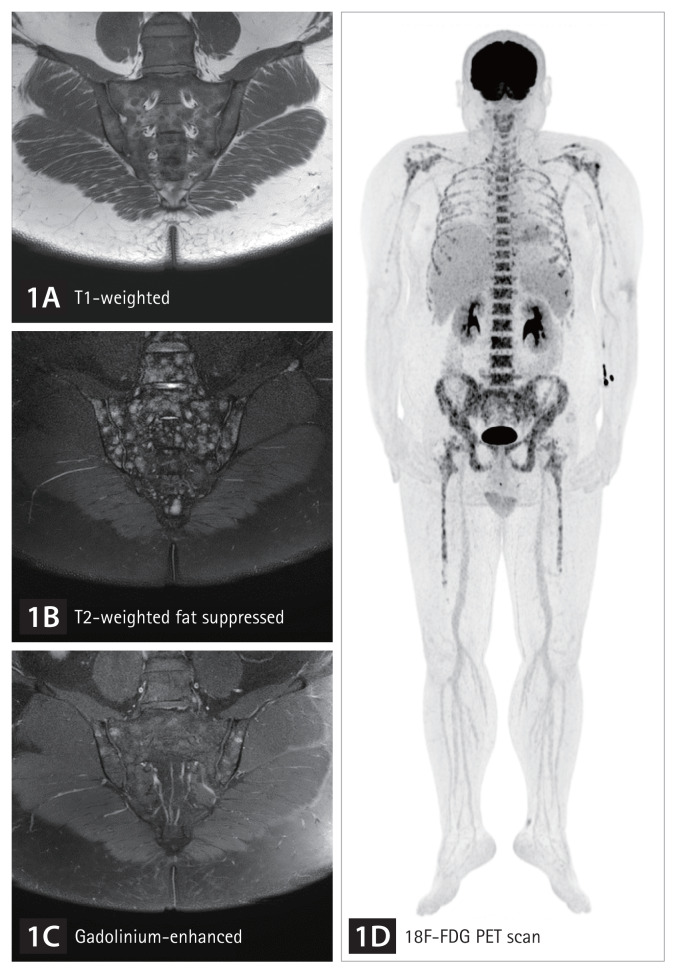

Hematologic malignancy detected on sacroiliac magnetic resonance imaging in a patient with inflammatory back pain.

炎性背痛患者骶髂核磁共振检查血液恶性肿瘤1例。